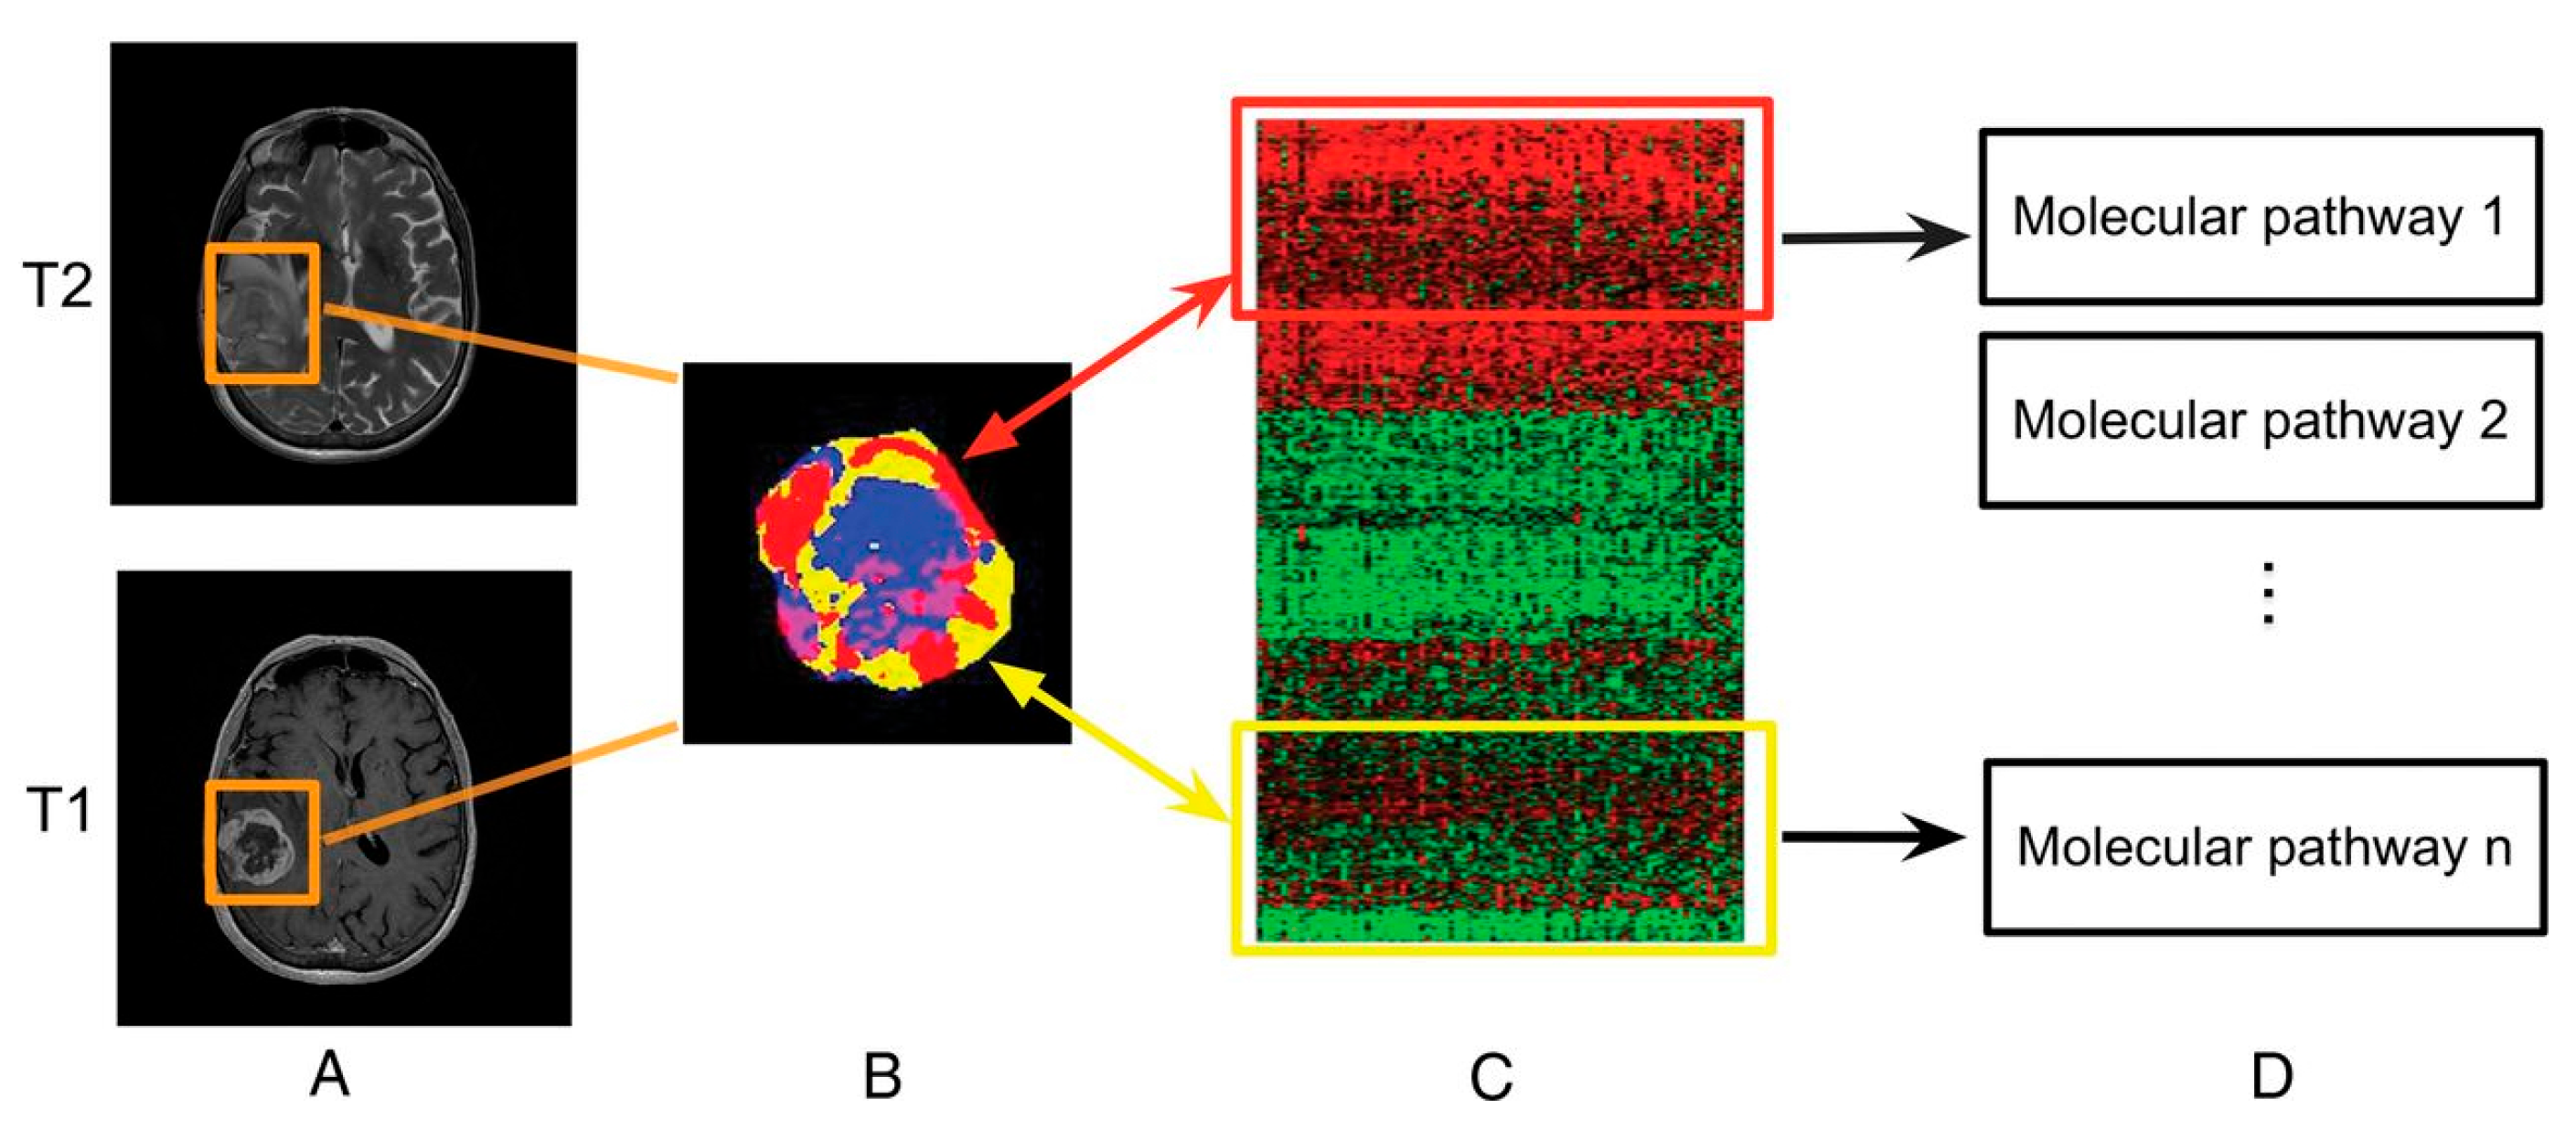

Radiomics is a fast-growing field in radiology where images from conventional radiological examinations are converted into extractable quantitative data that can then be used to decode the tumor phenotype for applications ranging from improvement of the diagnosis to the prognosis, to the prediction of the response to treatment [129]. In that field, radiogenomics refers to a specific application where imaging features are linked to genomic profiles (Figure 14) [130].

Figure 14.

Linking subregional imaging to molecular profiles in GB. In this example, tumor subregions (B) are defined by jointly clustering on contrast-enhanced T1WI and T2WI (A). These subregions correspond to red (high T1WI and high T2WI), yellow (high T1WI and low T2WI), blue (low T1WI and high T2WI), and pink (low T1WI and low T2WI) areas. The defined tumor subregions enable quantitative spatial characterization, offering a means to noninvasively assess specific molecular activities (C) with enriched molecular pathways (D) [139].